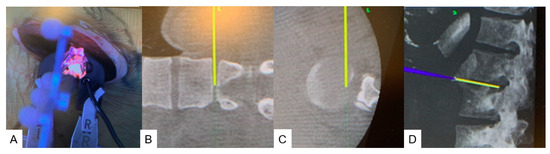

2.4. Surgery

2.4.1. Anterior Discectomy

2.4.2. Posterior Osteotomy